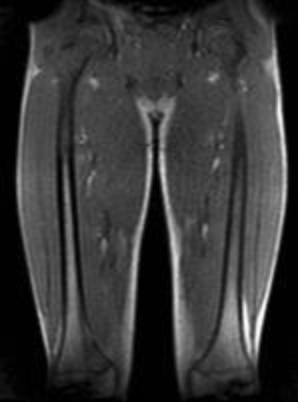

| COR | T1 | YES | YES | Cover from hip joint to knee joint in a single FoV |

| COR | T2 | YES | YES | Cover from hip joint to knee joint in a single FoV |

| COR | STIR | YES | YES | Cover from hip joint to knee joint in a single FoV |

- Must cover entire femur (including femoral head and femoral condyles – it’s okay if femoral heads are only imaged on the pelvic portion of the exam, if a dedicated Pelvis MR was also done). This is because the grading system takes marrow signal in both the proximal and distal femora into account.

- You can change the number of slices, TR, FoV, etc. to get scan into a single acquisition.

- DO NOT CHANGE SLICE THICKNESS OR GAP.